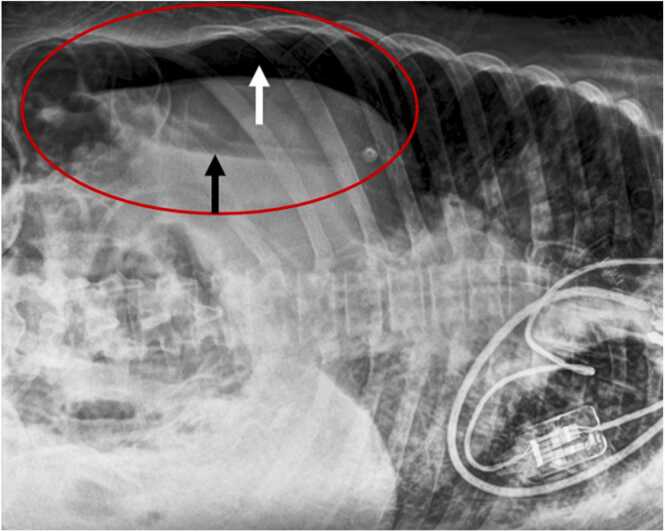

Abstract Image